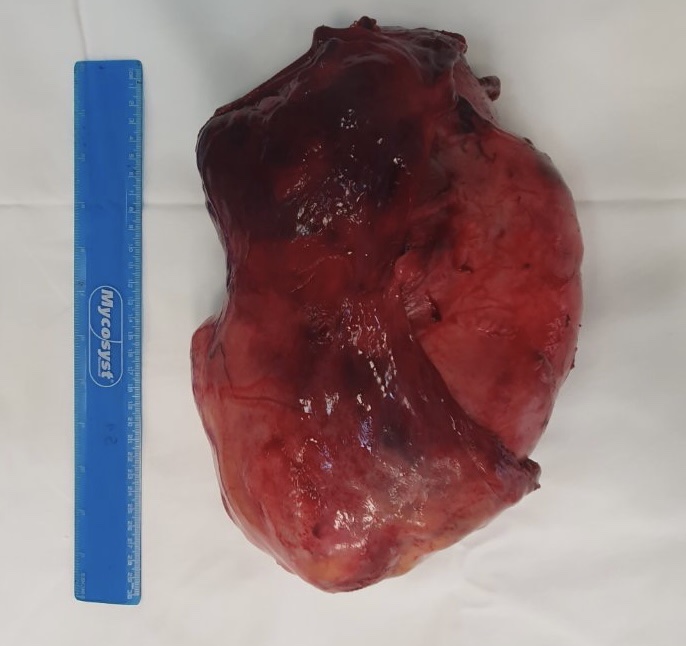

O tumoră de aproape 5 kg (4,680 kg) localizată în cavitatea pleurală a fost înlăturată cu succes de către chirurgii toracici ai IMSP SCR ”Timofei Moșneaga”. Din cauza volumului mare al formațiunii tumorale, accesul spre ea a fost practic imposibil. În pofida acestui fapt, datorită experienței și profesionalismului echipei SCR, intervenția chirurgicală a decurs reușit. Pacienta a fost o femeie de 61 de ani.

Am recurs la intervenție chirurgicală clasică prin toracotomie antero-laterală din dreapta. La deschiderea cavității pleurale depistăm o formațiune tumorală dură, destul de mare, care făcea practic imposibil de a avea acces în cavitatea pleurală la originea acestei tumori. Cu dificultate am introdus instrumentele și s-a început mobilizarea tumorii. După ce a fost mobilizată această formațiune de volum, practic mai mult orb, pe baza simțului și a instrumentelor am determinat că este o formațiune care crește din mediastinul anterior cu coborârea în cavitatea pleurală și comprimarea totalmente a plămânului. Plămânul drept al pacientei practic nu funcționa, el era comprimat totalmente. După ce am mobilizat această tumoare a apărut o altă problemă, nu puteam să o extragem” a explicat chirurgul, șeful Secției Chirurgie Toracică, Alexandru Toma.

După ce au mai lărgit incizia, medicii au izbutit să extragă tumora. Operația a durat aproximativ 3 ore.

Am efectuat și timectomie, deoarece tumora avea originea în glanda timus, care este localizată pe pericard. Operația a decurs destul de bine, fără pierderi de sânge, fără complicații intraoperatorii. Pacienta deja a doua zi a fost transferată din terapia intensivă în secția de profil. În practica noastră întâlnim des tumori mediastinale, dar atât de mari, aproape 35-40 cm, cu 25 cm în diametru - mai puține” a adăugat Alexandru Toma.